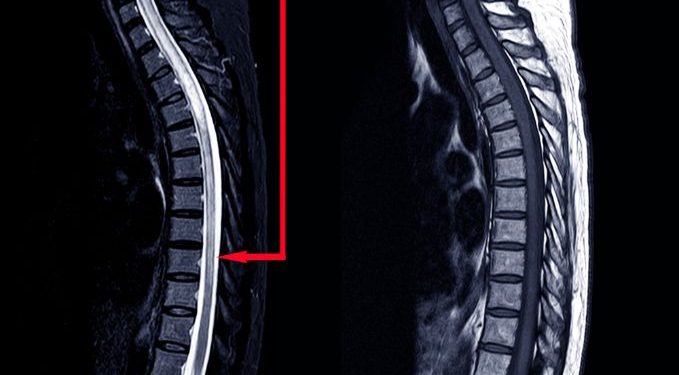

Spine tumors are cancerous growths that develop in the spinal cord, spinal nerves or bone. They can cause permanent damage to the spine and the spinal nerves and can affect the ability to walk and move. In addition, a spinal tumor may also cause pain. A diagnosis of a spinal tumor requires that the patient visit a medical provider for evaluation. This may include an MRI scan, which will show the presence of the tumor and its position in the spinal cord.

Spine tumors can be either primary (growing inside the spine) or secondary (growing outside the spinal column). Primary tumors grow slowly and typically only last a few weeks to years. Secondary tumors can spread and cause pain and neurological deficits. Patients with spinal tumors will have regular checkups, but in some cases they will need surgery to remove a tumor.